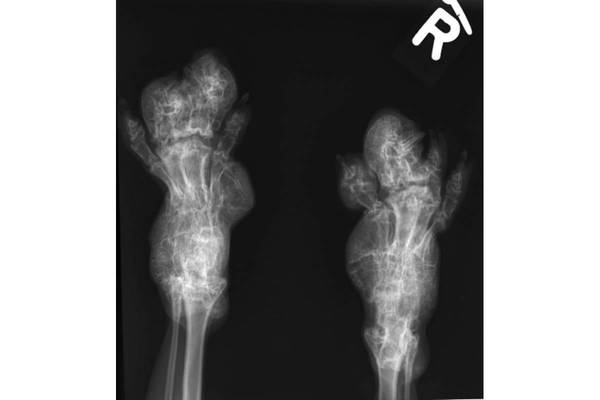

Das besondere (Qualzucht-)Merkmal der Scottish Fold sind die „gefalteten“ Ohren. „Sie sind das sichtbare Zeichen einer unheilbaren Erbkrankheit“, erklärt Tierarzt Manfred Hochleithner. „Was süß ausschaut, bedeutet für die Tiere höllische Qualen.“ Die sogenannte Osteochondrodysplasie (OCD) sorgt für Beeinträchtigungen wie Gelenksschwellungen, verdickte und missgestaltete Gliedmaßen sowie eine abnorme Körperhaltung und Gangart. Kostspielige tierärztliche Behandlungen sind die Folge. „Oftmals bleibt leider nur die Euthanasie als einzige Möglichkeit, das Leid zu beenden“, so Hochleithner.

Die Berichte aus der tierärztlichen Praxis zeigen eindrücklich, wie sehr die Tiere für dieses falsche Schönheitsideal gequält werden. Da ist etwa der Fall des jungen Katers, gerade erst ein Jahr alt, der nicht mehr gehen konnte. „Die Pfoten waren extrem verdickt, schmerzhaft, es war keine Zehenbewegung möglich“, berichtet der behandelnde Tierarzt. „Die Zehen waren teilweise verformt, die Krallen unbeweglich, zum Teil eingewachsen, die Pfoten steinhart und aufgeschürft.“ Nach einer Woche vergeblicher Hoffnung auf Besserung des Zustands wurde das Tier eingeschläfert.